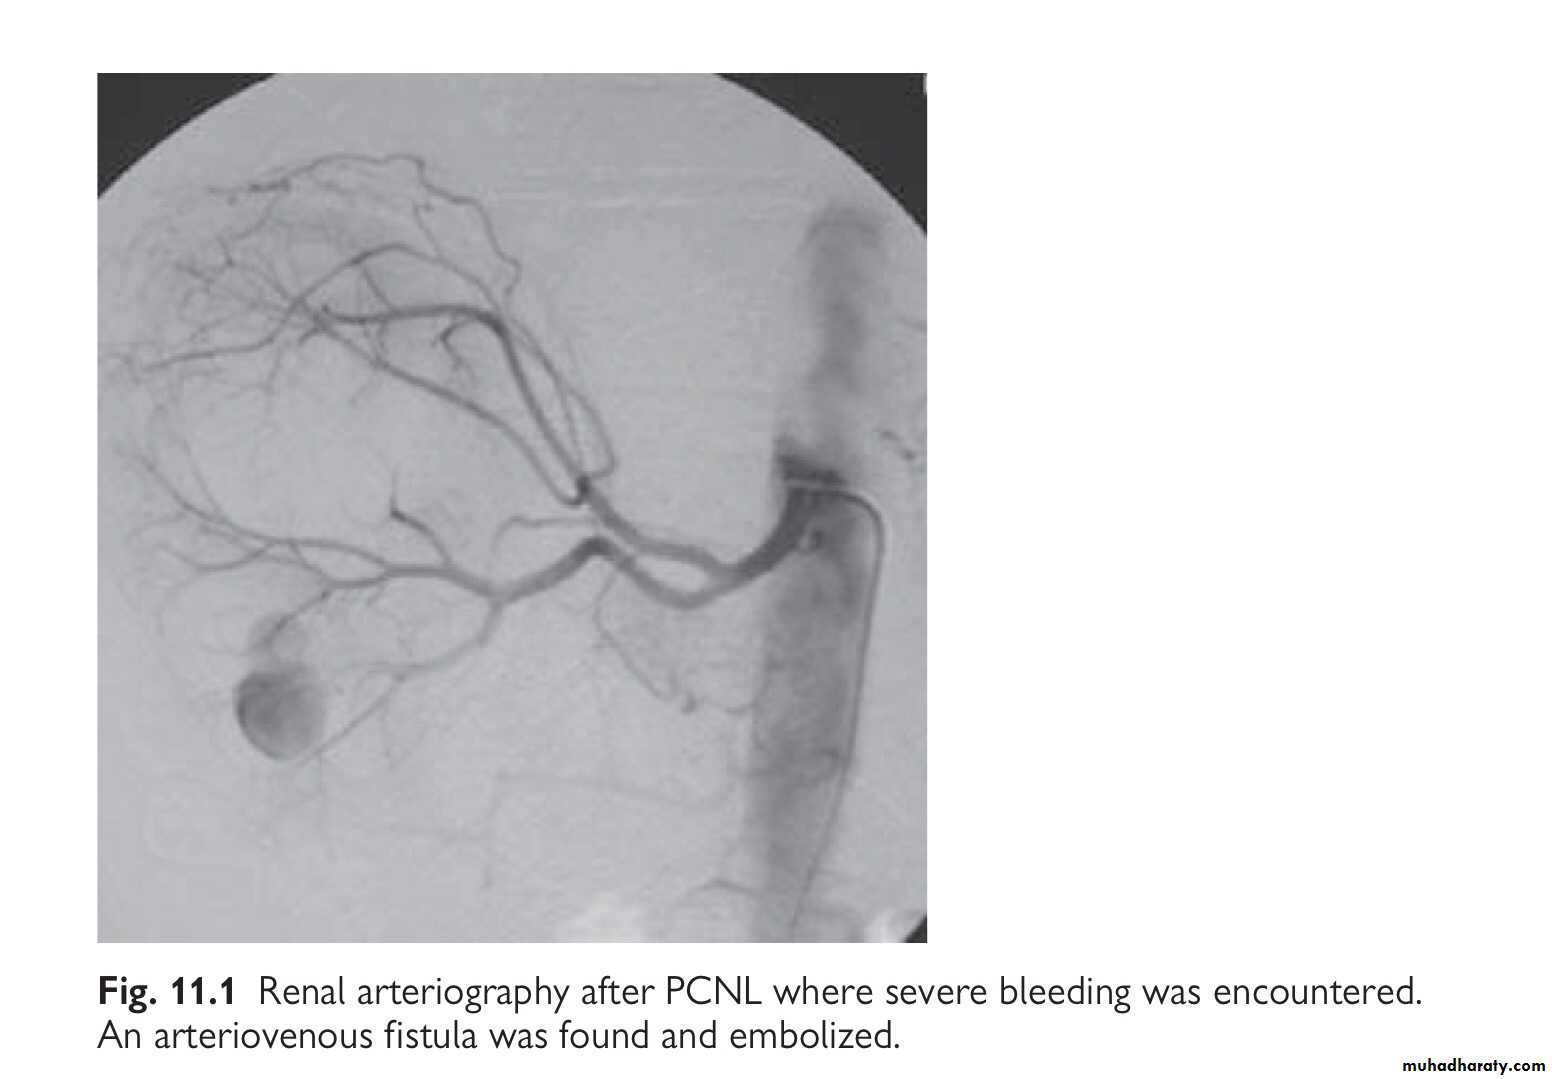

Using CT, renal injuries can be staged according to the AmericanAssociation for the Surgery of Trauma (AAST) Organ Injury Severity Scale. Higher inju- ry severity scales are associated with poorer outcomes.

Parenchymal laceration, involving cortex, medulla and collect- ing system OR renal artery or renal vein injury with contained haemorrhage.

Most blunt (95%) and many penetrating renal injuries (50% of stab injuries and 25% of gunshot wounds) can be managed non-operatively.

High-grade (IV and V) injuries: can be managed non-operatively if they are cardiovascularly stable. However, grade IV and, especially, grade V injuries often require nephrectomy to control bleeding (grade V injuries function poorly if repaired).